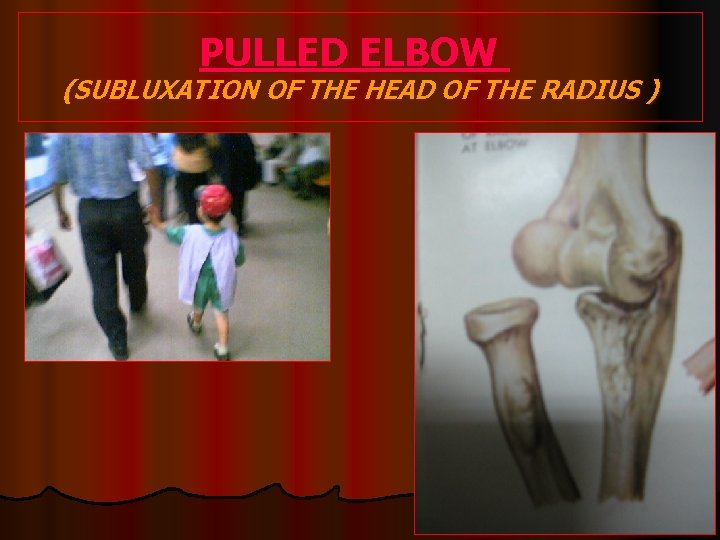

INJURIES AROUND THE ELBOW <<7 4 l l l l 1 - SUPRACONDYLAR FRACTURE 2 - DISLOCATION ELBOW 3 - FRACTURE OLECRANON 4 - FRACTURE HEAD RADIUS 5 - FRACTURES OF HUMERAL CONDYLES 6 - EPICONDYLE FRACTURE 7 - PULLED ELBOW 3 >>2 5 6 1 5

PULLED ELBOW (SUBLUXATION OF THE HEAD OF THE RADIUS )